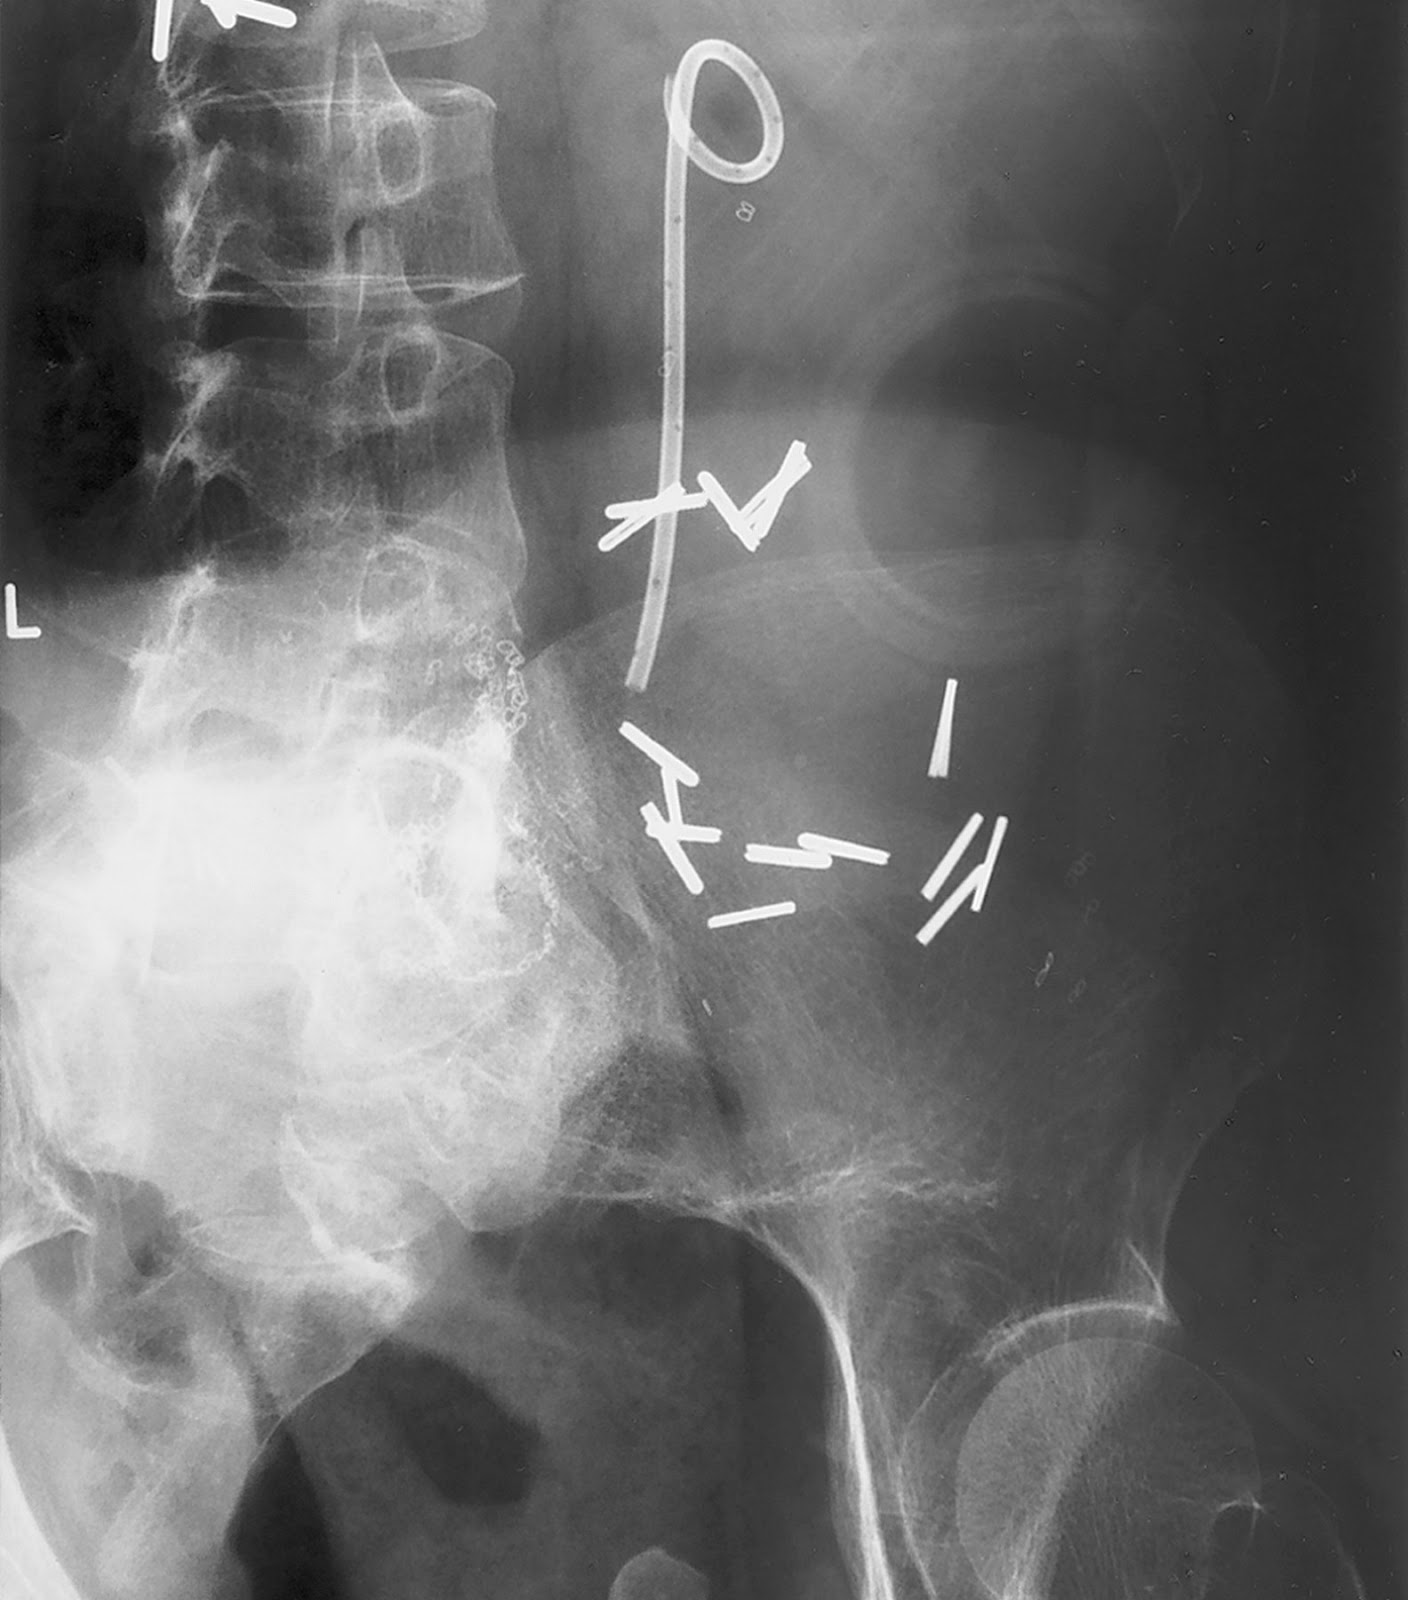

Dolor Intenso Por Catéter Doble J, , , , , , , 0, Radiografía de Doble Jota fracturado, cateterdoblejota.com, 1408 x 1600, jpeg, WebTambién es posible que el catéter produzca espasmos en la vejiga, debido a que el bucle o J que se encuentra en ella irrita su capa interna. Esto se va a traducir en. WebMadrid. Habitualmente los catéteres doble J son bien tolerados, pero en algunos casos provocan dolores intensos parecidos a los de un cólico renoureteral por. WebLa función del catéter doble J es asegurar el paso de orina del riñón hacia la vejiga cuando el uréter está obstruido. Esta obstrucción suele ser por una piedra, aunque puede ser., 20, dolor-intenso-por-cateter-doble-j, Novedades y Muebles WebTambién es posible que el catéter produzca espasmos en la vejiga, debido a que el bucle o J que se encuentra en ella irrita su capa interna. Esto se va a traducir en. WebMadrid. Habitualmente los catéteres doble J son bien tolerados, pero en algunos casos provocan dolores intensos parecidos a los de un cólico renoureteral por. WebLa función del catéter doble J es asegurar el paso de orina del riñón hacia la vejiga cuando el uréter está obstruido. Esta obstrucción suele ser por una piedra, aunque puede ser.